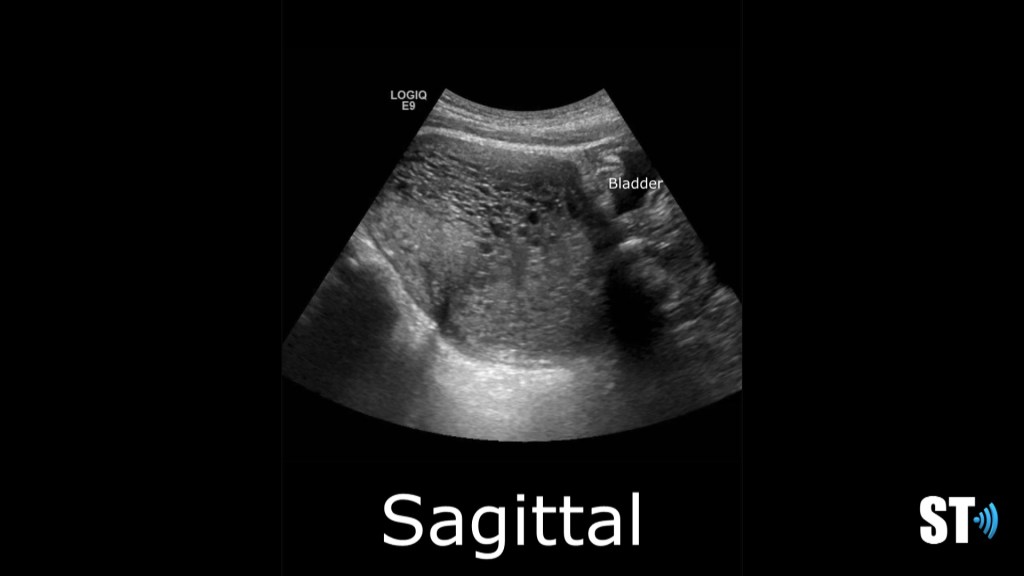

Complete mole transverse and sagittal images showing an enlarged, round uterus with a complex multi cystic endometrial complex. Hcg was 25,344